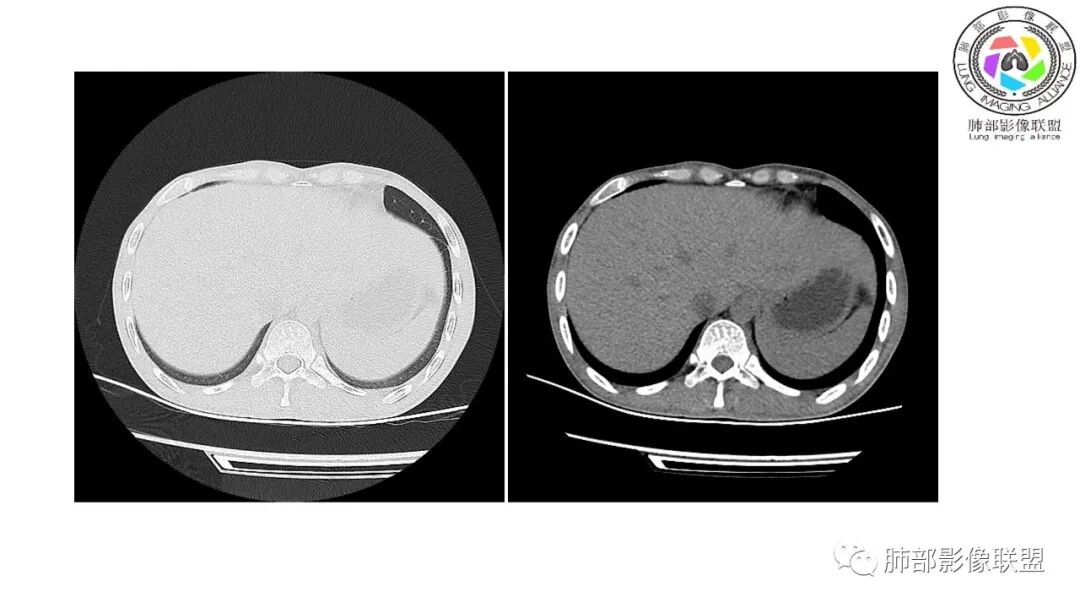

以下为2021-7-15日上腹部CT

影像与临床:1.青年男性,HlV阳性,颜面部皮疹(未提供皮疹图像)、发热(高热),实验室CRP、PCT高,T-Spot阴性。2.右肺下叶空洞结节,壁厚不均,边界清楚,其内线状影,未见液平及钙化,未见卫星灶,纵隔淋巴结增大,双侧腋窝见增大淋巴结。心腔内低密度提示贫血可能。肝脾影增大,未见结节影及块影。腹膜后见多发增大淋巴结。

综合分析:本例肺部影像学改变并不具有特征性,空洞性病灶须与多种疾病鉴别,但年轻HIV阳性患者,高热,皮疹,肝脾增大,纵隔、腋窝、腹膜后见多发增大淋巴结等都强烈提示马尔尼菲篮状菌感染的可能性。